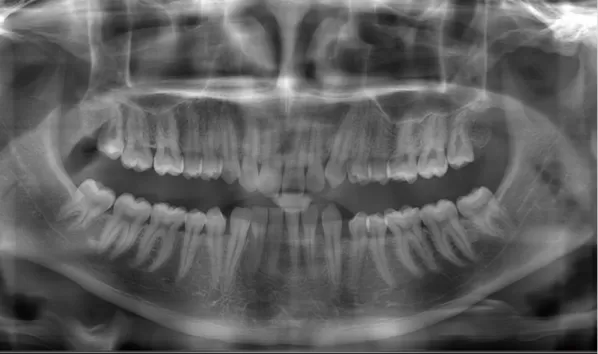

X-rays before treatment

[Panoramic Radiography/Lateral Cephalogram]